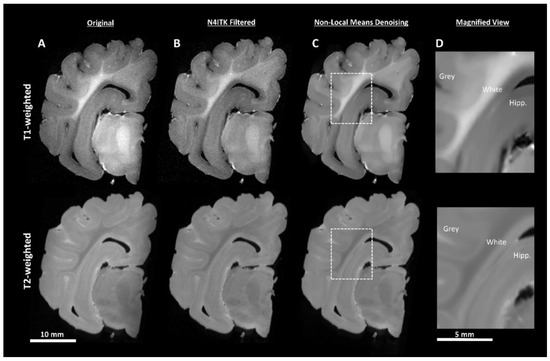

2.4.1. Pre-Processing